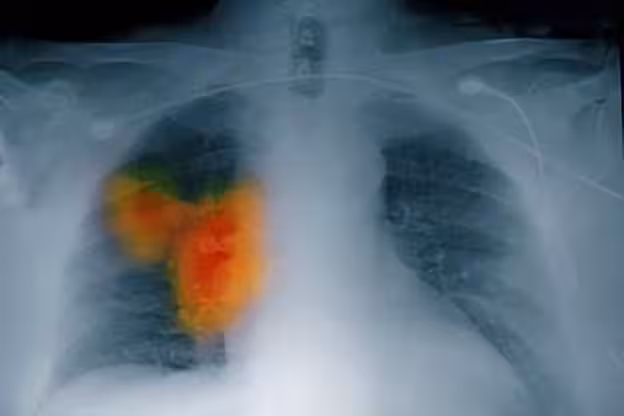

58歲女子確診肺癌,強忍淚水坦言:手部早出現了問題,沒有多重視!